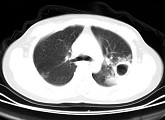

- 单项选择题男,25岁, 咳嗽,咯血近1周, 午后低热1个月余,CT检查如图, 最可能的诊断为 ( )

B、双上肺结核,左上肺结核空洞形成